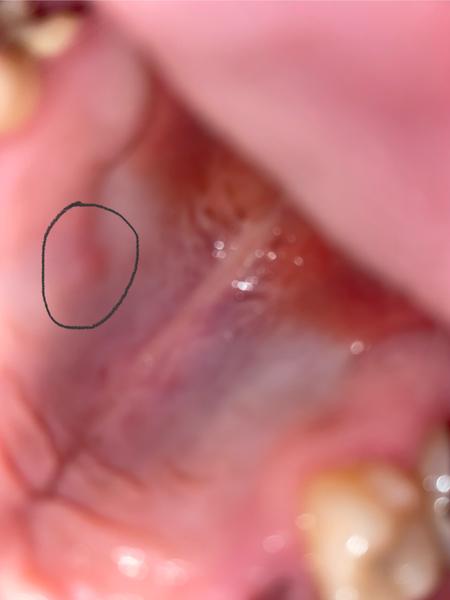

Ahojte, urobila sa mi takáto Hrčka na podnebí, mám ju už asi mesiac, zubárovi som to ukázal ale povedal že nevie čo to je a moc to ďalej neriešil. Vedeli vy ste mi poradit poprípade či ste nemali niečo podobne niekto?

Vďaka.